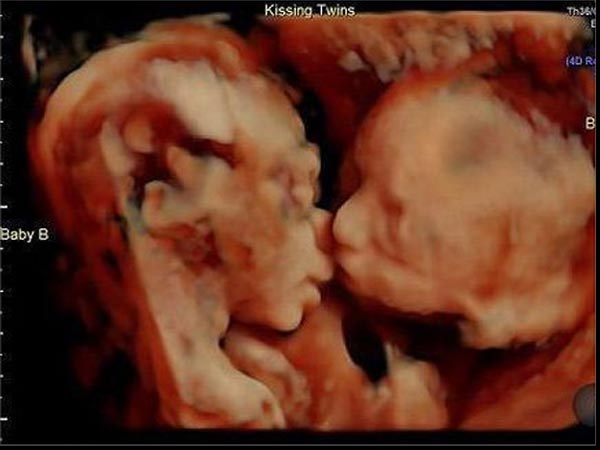

அல்ட்ராசவுண்ட் ஸ்கேன் செய்வது குழந்தையை பாதிக்குமா?

அடிக்கடி அல்ட்ராசவுண்ட் ஸ்கேன் செய்வது சரியானதா என்பது பற்றி கொடுக்கப்பட்டுள்ளது.

அல்ட்ராசவுண்ட் ஸ்கேன் பல வருடங்களாக பயன்படுத்தப்பட்டு வருகிறது. ஆனால் இதனால் ஆபத்தான விளைவுகள் ஏற்படுவதற்கான எந்த ஒரு ஆதரமும் இல்லை.

மேலும் ஸ்கேன்கள் மருத்துவர்களுக்கு குழந்தையின் வளர்ச்சி, குழந்தையின் நிலை போன்ற அனைத்து விவரங்களையும் துல்லியமாக தருகிறது. இது குழந்தையை பற்றி மருத்துவர்கள் முழுமையாக அறிந்து கொண்டு அதற்கு ஏற்றாற் போல் சிகிச்சையளிக்க உதவியாக இருக்கிறது.

- உங்களுக்கு இரட்டை குழந்தை அல்லது அதற்கு மேற்பட்ட குழந்தைகளாக இருக்கலாம்.